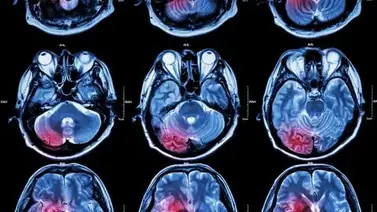

2001online - derrame cerebral

Cada 3 minutos y 11 segundos, alguien en el mundo sufre un derrame cerebral, un evento médico grave que requiere atención inmediata. El neurólogo Dr. Jonathan Solomonow enfatiza la importancia de reconocer las señales tempranas de un accidente cerebrovascular.